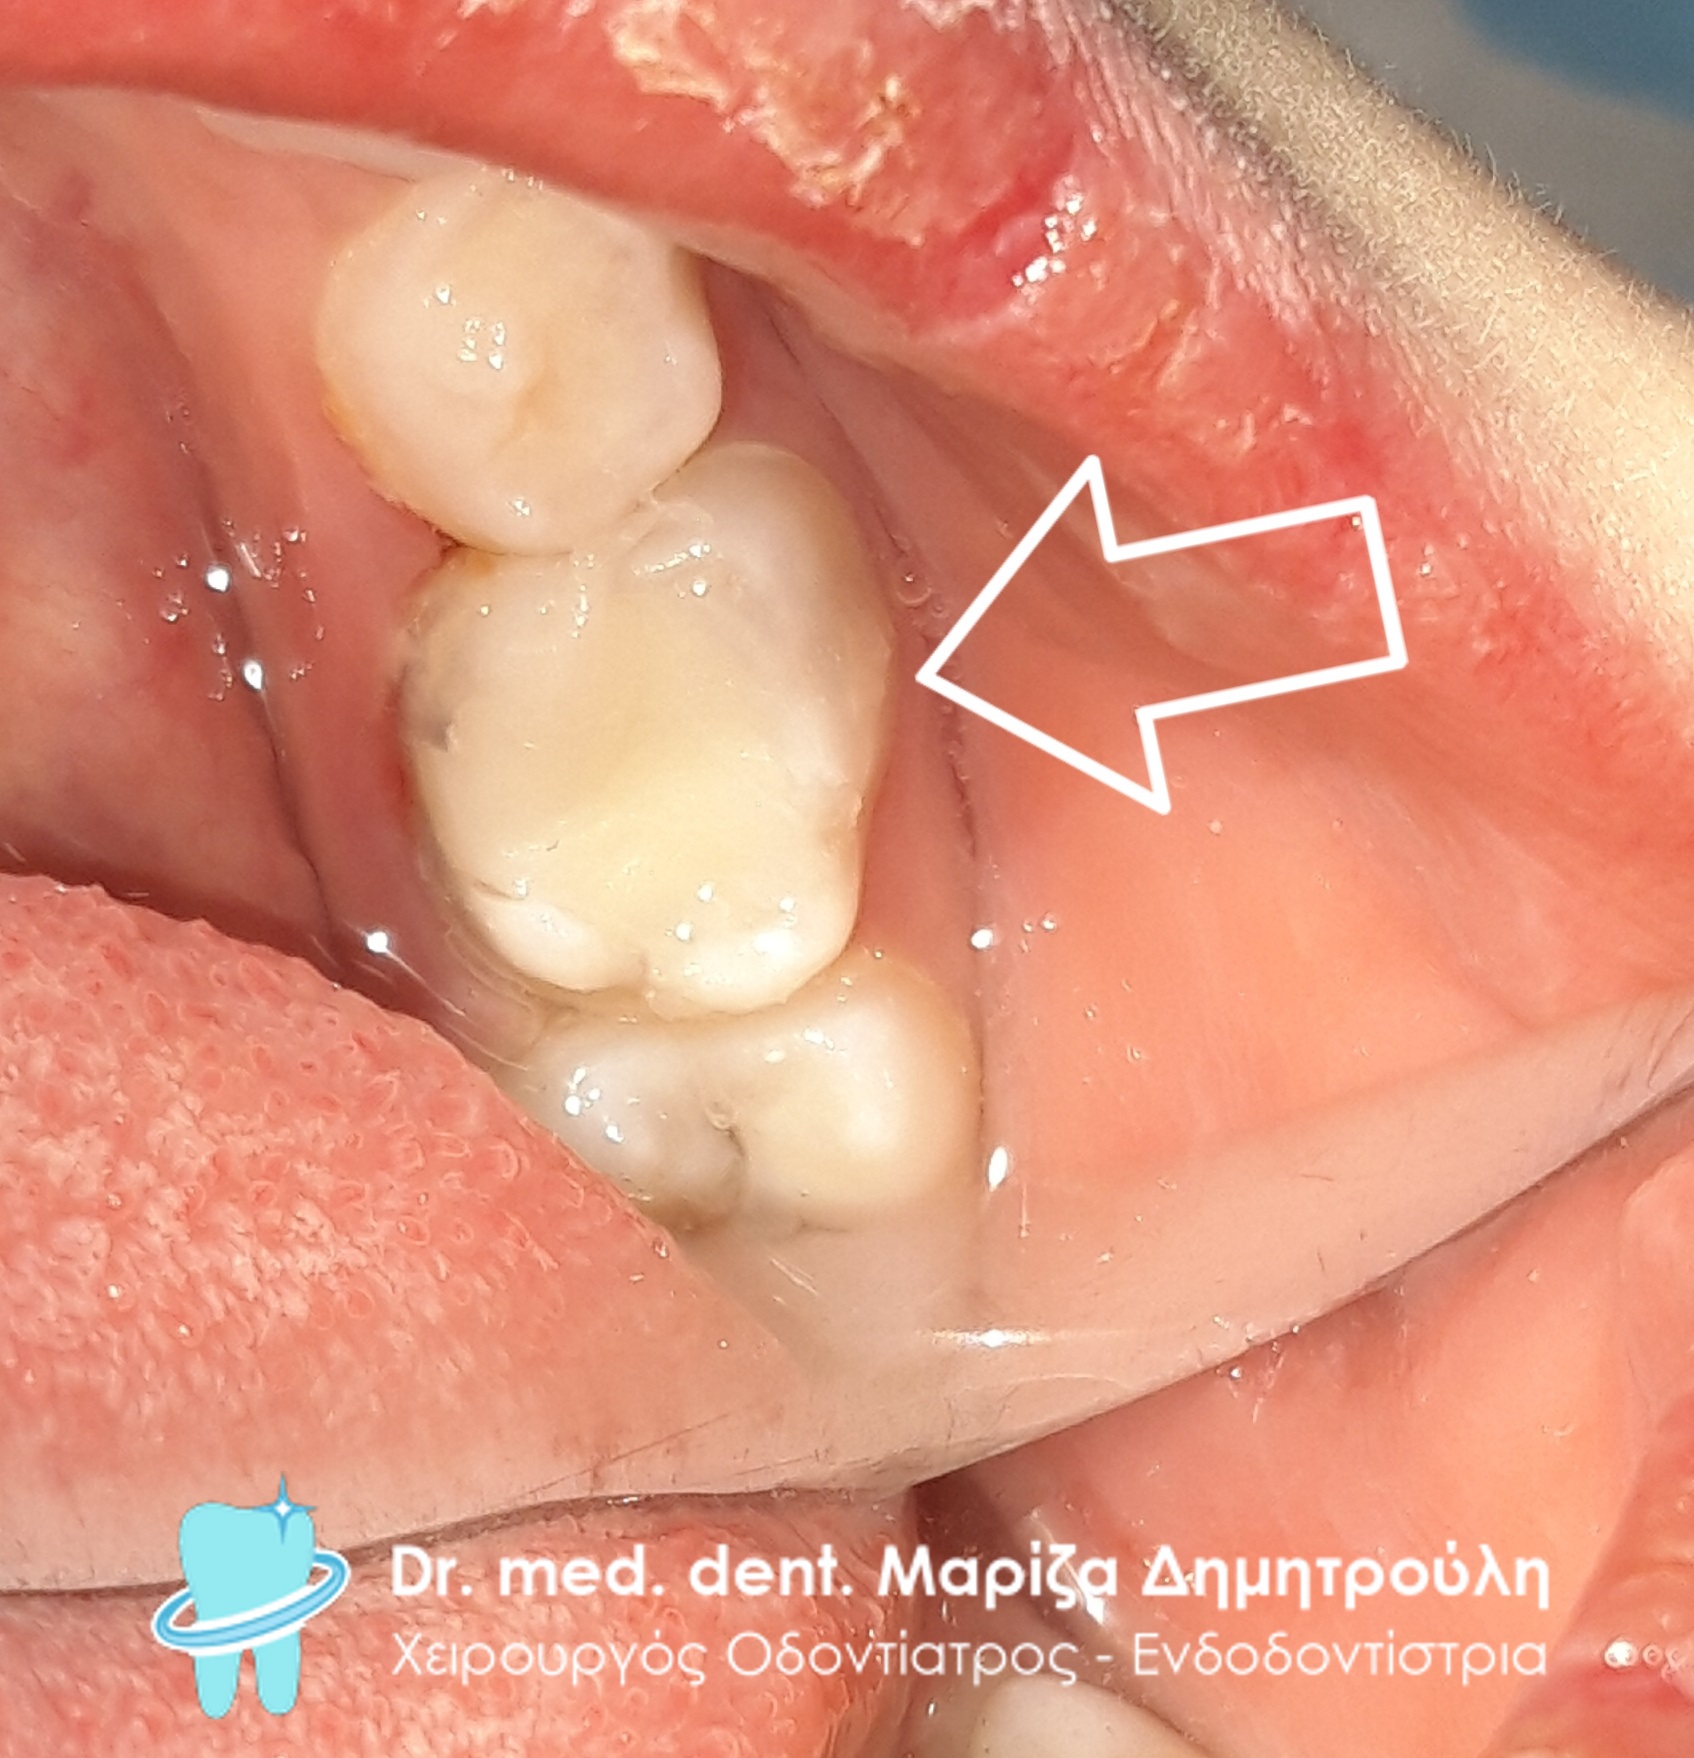

Το μικρό κορίτσι επισκέφτηκε το ιατρείο με έντονο πόνο στην αριστερή πλευρά της κάτω γνάθου. Η κλινική εξέταση αποκάλυψε όπως δείχνει και η εικόνα της αρχικής κλινικής κατάστασης την παρουσία μιας βαθιάς και εκτεταμένης τερηδονικής αλλοίωσης. Μετά τη χορήγηση τοπικής αναισθησίας απομακρύνθηκαν οι τερηδονισμένοι οδοντικοί ιστοί από το δόντι. Κατά την αφαίρεση της τερηδόνας αποκαλύφθηκε τοπικά το νεύρο του δοντιού, δηλαδή ο πολφός του δοντιού. Η μητέρα ενημερώθηκε αναλόγως και αμέσως πραγματοποιήθηκε η πολφοτομή του νεογιλού δοντιού. Στο σημείο της αποκάλυψης του πολφού τοποθετήθηκε ειδικό φάρμακου και στη συνέχεια η διαδικασία ολοκληρώθηκε με την ανασύσταση του οδοντικού ελλείμματος με λευκό σφράγισμα ρητίνης. Στο ραντεβού επανελέγχου η μικρή ασθενής δεν πονούσε καθόλου.

ΠΡΙΝ